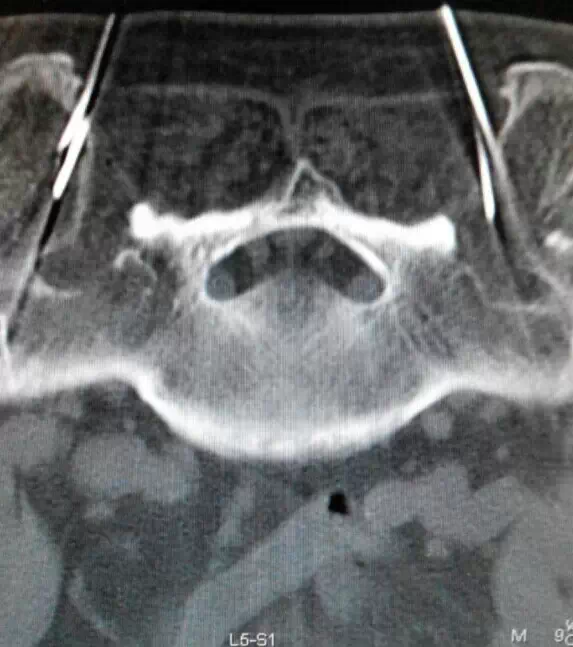

5、四川奥斯迪康骨医院治疗方法:CT引导射频热凝术

治疗优势:安全、疗效好、不易复发、无副作用、费用比手术治疗低、创伤小、痛苦小、治疗时间短。